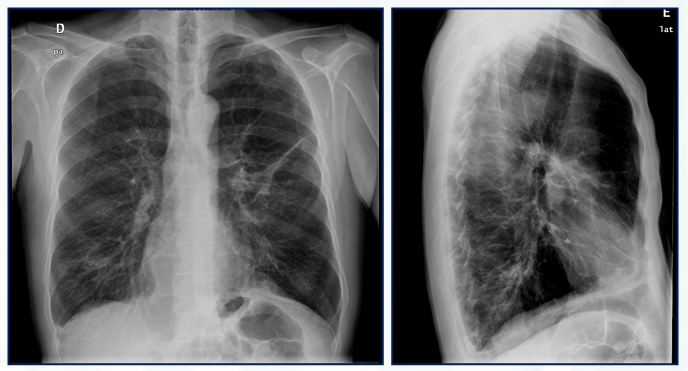

Qual o achado desse Rx de tórax PA e perfil?

Hiperinsuflação pulmonar, frequente na DPOC.

• Aumento do diâmetro AP do tórax

• Retificação das cúpulas diafragmáticas

• Aumento do espaço retroesternal

• Aumento do espaço intercostal

• > 10 costelas posteriores

• Pulmões hipertransparentes

• Horizontalização das costelas

• Coração em “gota